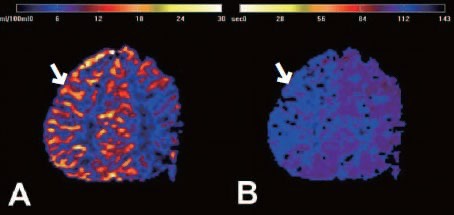

수술치료(뇌혈류 재건술, Revascularization surgery)

모야모야병의 핵심 치료는 뇌혈류 공급을 위한 새로운 통로를 만들어주는 수술입니다.

① 직접 우회술(Direct bypass)

• 측두동맥(STA)을 직접 뇌혈관(MCA)과 연결해 혈류를 즉시 공급하는 방식 • 성인에서 가장 많이 시행

• 수술 직후부터 혈류 개선 효과가 빠르게 나타납니다.

② 간접 우회술(Indirect bypass)

• 근육이나 막 조직을 뇌 표면에 붙여 그 조직에서 자라는 새로운 혈관이 뇌를 공급하도록 유도 • 소아에서 많이 사용

• 혈류 증가 효과가 나타나기까지 수개월이 필요합니다.

③ 혼합 우회술(Combined bypass)

• 직접 + 간접 방법을 동시에 시행하는 방식

• 빠른 효과 + 장기 안정성을 동시에 노릴 수 있는 방법입니다.